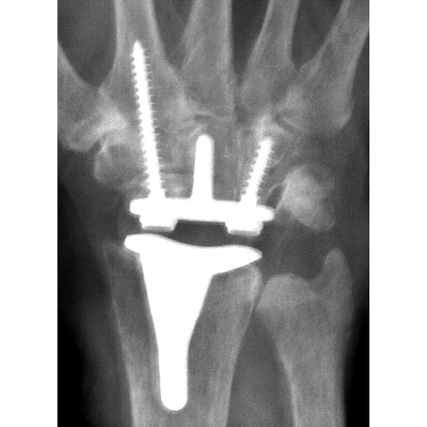

The system consists of components to replace the articulation of the distal radius and proximal row of carpal bones of the wrist joint and corresponding instrumentation. The components are intended to be implanted together as a system, not individually as hemiarthroplasty components.

The radial component is made of Cobalt Chrome Molybdenum Alloy (CrCoMo) and has a concave articulating surface, and is fixed through a stem that is inserted and cemented into the radial intramedullary canal.

The carpal implant consists of a titanium carpal plate, which is fixed into the carpal bones with a cemented central peg and two titanium screws and locking caps. A convex Ultra-High-Molecular-Weight Polyethylene (UHMWPE) bearing is locked onto the carpal plate to articulate with the radial component.